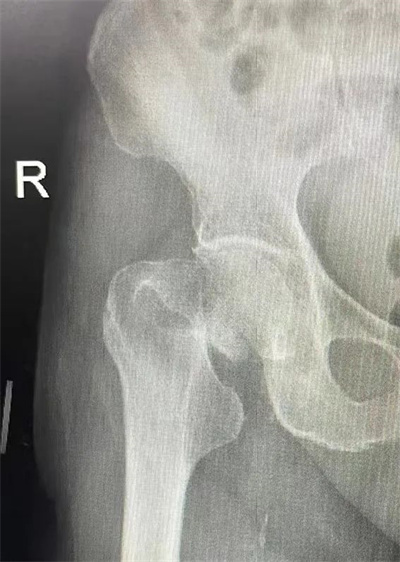

股骨头坏死又称为股骨头缺血性坏死或股骨头无菌性坏死,指股骨头血供受损或中断,导致骨髓成分及骨细胞死亡及随后的组织修复,继而导致股骨头结改变及塌陷,引起患者髋关节疼痛及功能障碍的疾病,也是造成青壮年髋关节残疾的常见疾病之一。

医生一般会要求您进行髋部的X光检查或磁共振成像(MRI)检查。MRI是目前早期诊断和识别骨坏死程度的最佳检查,绝大多数的髋关节疾病都可以通过MRI来诊断。根据您的情况,可能还需要同时进行腰椎、下肢其他部位甚至全身的检查等等。